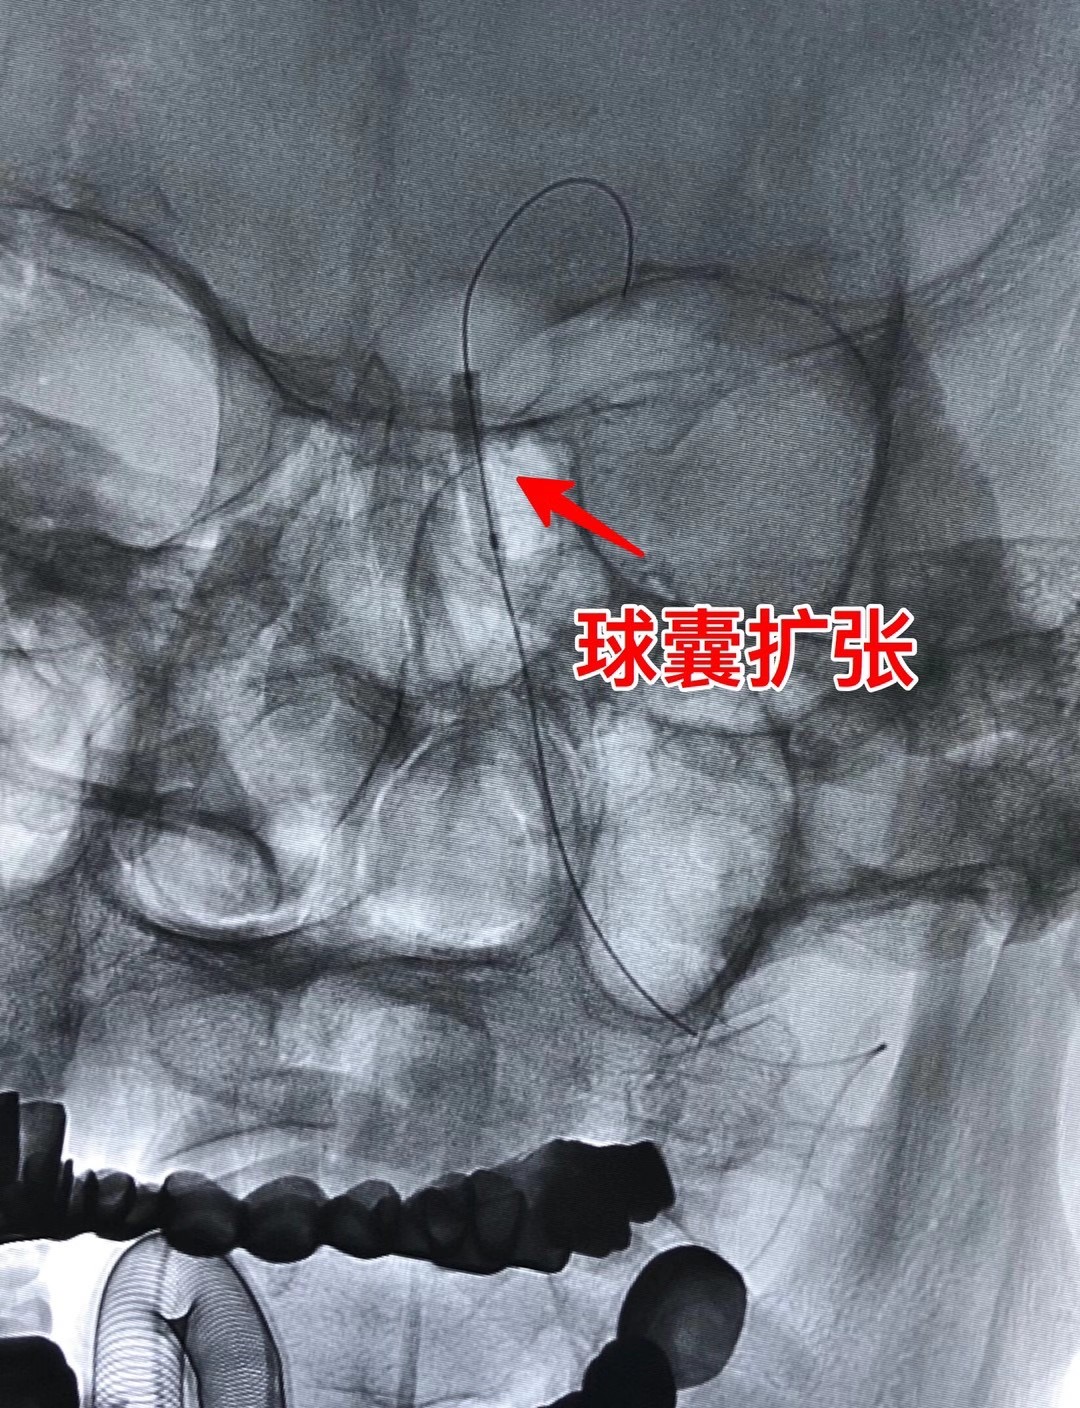

张某,71岁,1年前因头晕就诊于当地医院,行头颅MRI诊断小脑梗死,虽按照脑血管病二级预防给予药物对症治疗,但头昏症状持续存在,近期甚至出现发作性意识丧失,患者症状影响生活不说,更是让家人担心其生命安全,为进一步诊治,慕名就诊于神经内科王新来主任脑血管病专科门诊,王主任细致地询问了患者病史,认真地审阅了头颅影像资料后,发现了患者发病的元凶——基底动脉狭窄,随即将患者收住入院,入院后及时、全面完善相关检查,提示患者基底动脉供血区脑灌注严重不足,于是神经内科团队进行了术前讨论,明确了手术的可行性和必要性,王新来主任医师、雷辉主任医师带领介入小组团队,制定了周密的手术方案,并与患者及家属做了充分的术前沟通,于2020818日在介入室为患者实施手术,术后患者脑灌注明显改善,头昏症状显著缓解,已于近日顺利出院。

(患者全脑血管造影提示基底动脉狭窄75%  底动脉狭窄的Tips

雷辉主任医师介绍:基底动脉是脑内重要血管,由左、右两支椎动脉汇合而成,常称为椎基底动脉系统。这个系统在颅腔内的分支为脊髓、脑干、小脑和间脑后部供血。基底动脉狭窄导致后循环缺血,临床上往往会表现为如头痛、头晕、黑曚等症状,重者还可能出现四肢瘫痪、意识障碍,甚至死亡。重度基底动脉狭窄的患者,达到手术指征时理论上应尽早行支架植入成形治疗解除狭窄,预防危及生命的卒中复发。但基底动脉因其特殊的解剖结构,支架置入,面临着分支多、斑块移位可能会引起雪犁效应导致穿支动脉闭塞加重病情,斑块脱落至远端甚至会造成严重的致死性并发症即基底动脉尖综合征,也有可能会出现局部的脑血流过度灌注出血等等各种风险,因此属于血管介入领域的超高难度手术,该技术也标志着神经介入领域的最高技术水平。